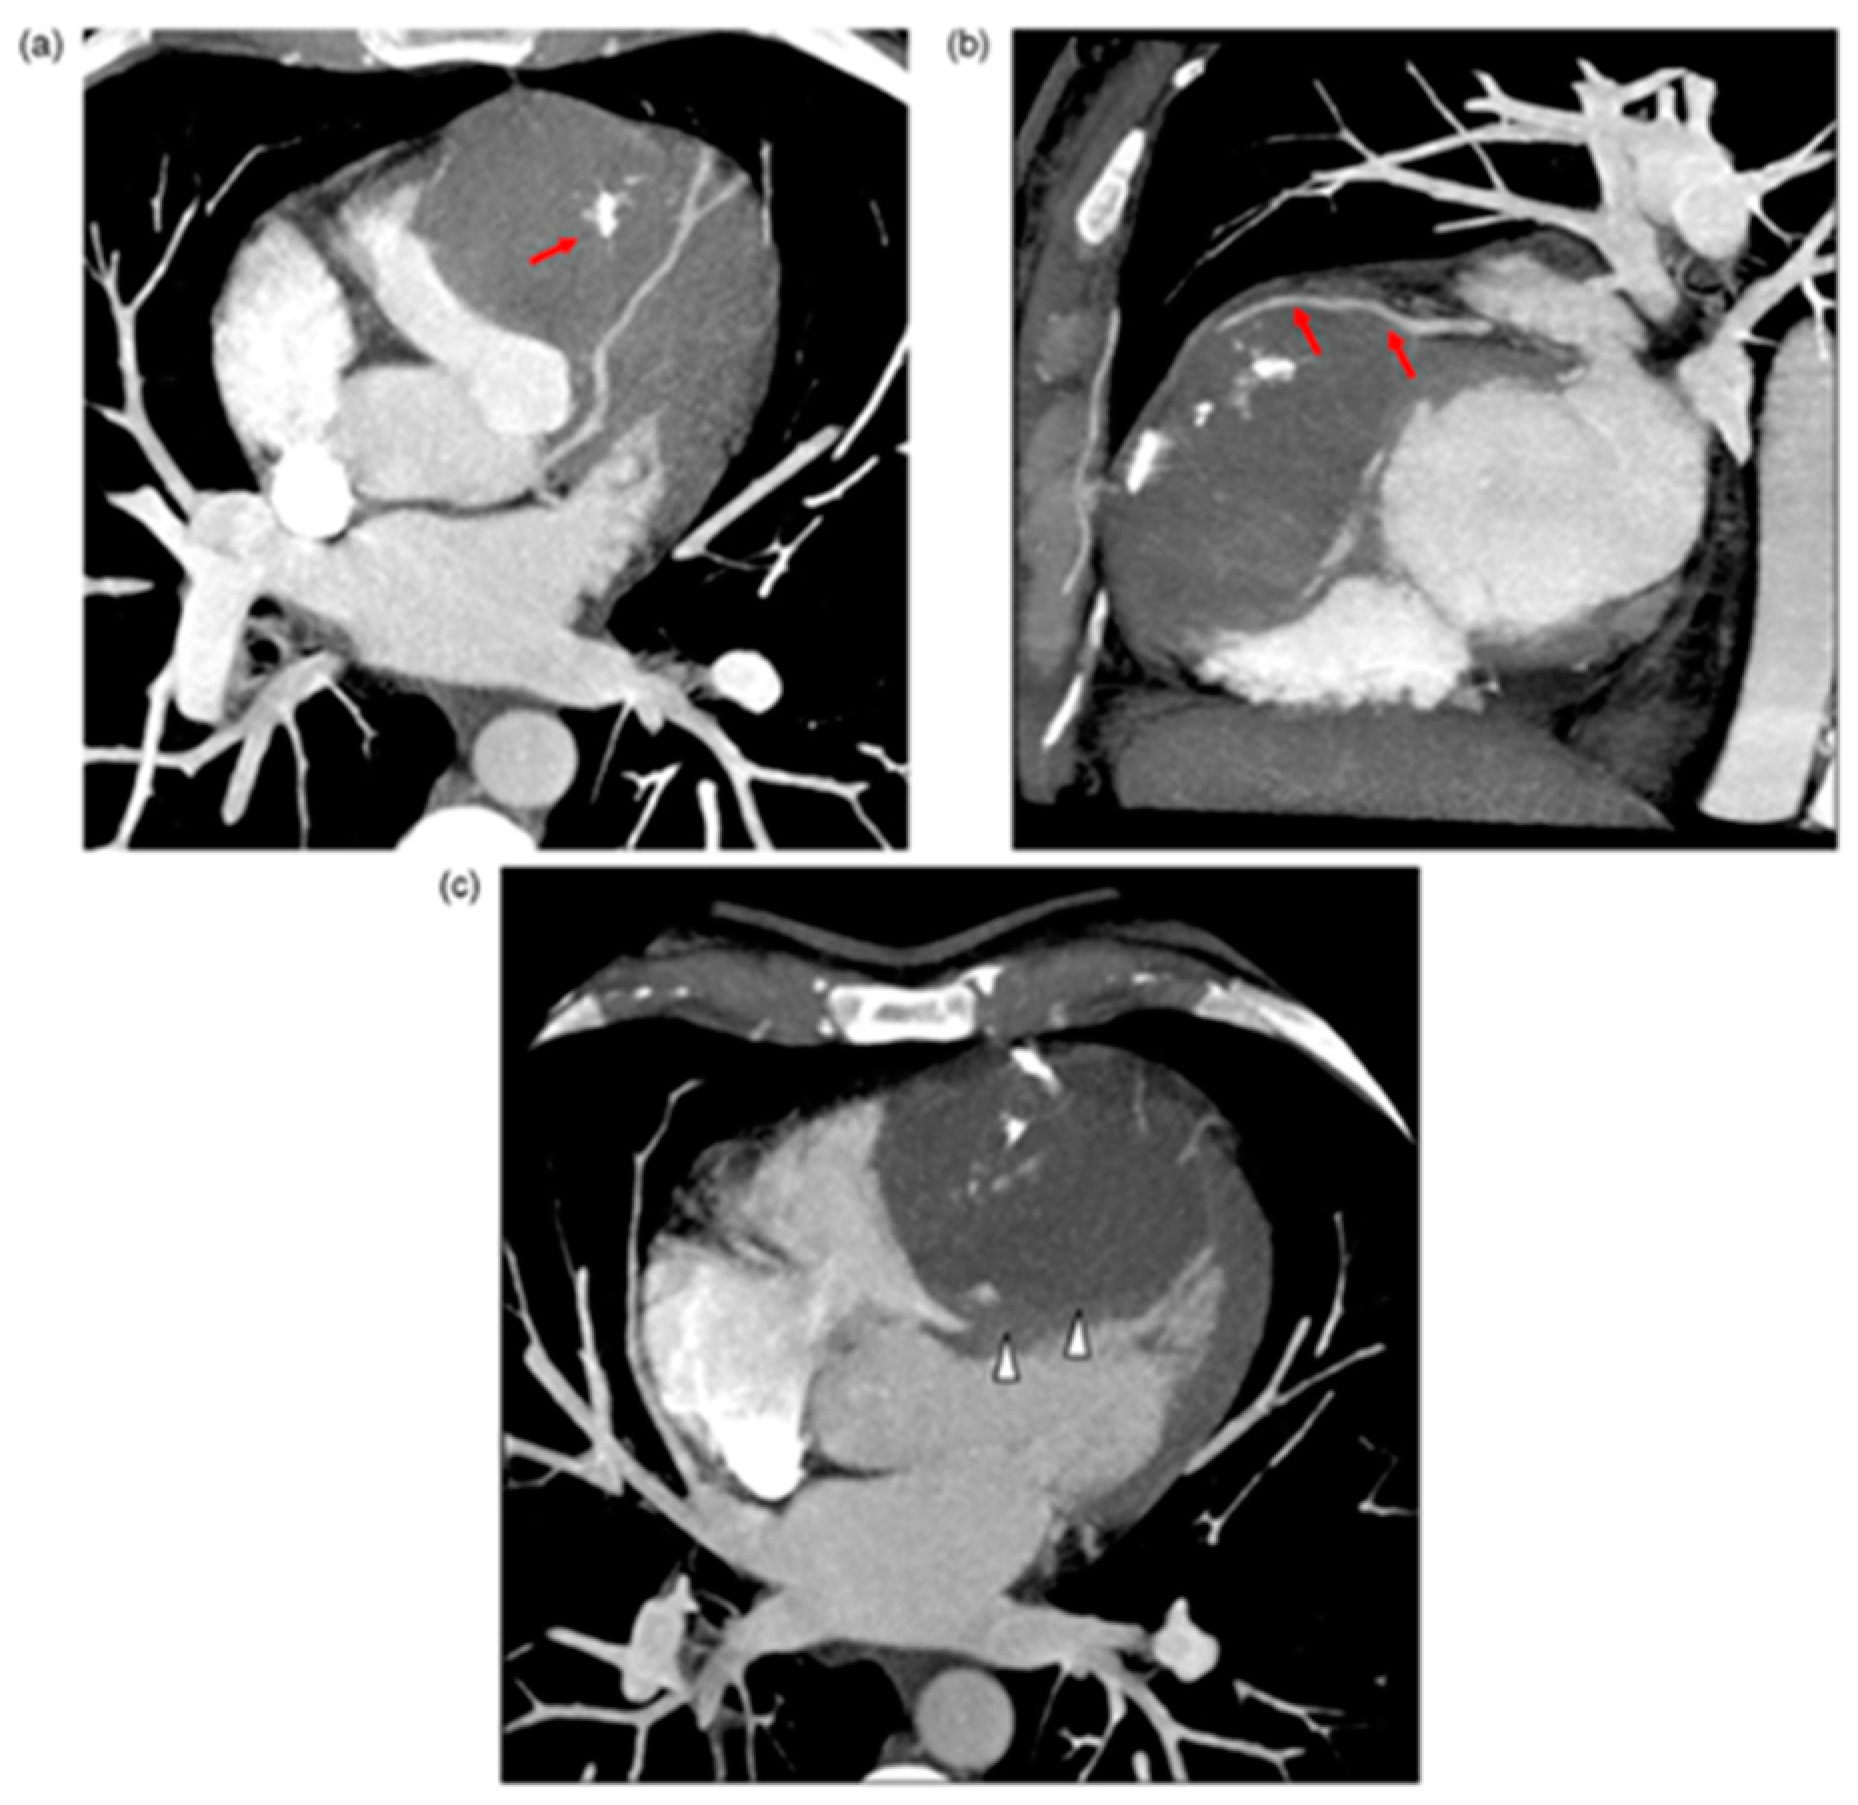

4.6. Other

- Subbaraman, S.; Rajan, S.C.; Veeraiyan, S.; Natarajan, P. Imaging Findings of Lipomatous Hypertrophy of the Interventricular Septum: A Case Report. Clin. Med. Insights Case Rep. 2021, 14, 11795476211024848. [Google Scholar] [CrossRef]

- Stéphant, E.; Anac, S.; Philippeb, D. Inter-ventricular septal cardiac fibroma in an adult: MR and MDCT features with pathologic correlation. Eur. J. Radiol. Extra 2008, 67, e103–e106. [Google Scholar] [CrossRef]

- Fennira, S.; Kamoun, S.; Besbes, B.; Ben Mrad, I.; Zairi, I.; Ben Moussa, F.; Mzoughi, K.; Kraiem, S. Cardiac hydatid cyst in the interventricular septum: A literature review. Int. J. Infect. Dis. 2019, 88, 120–126. [Google Scholar] [CrossRef]